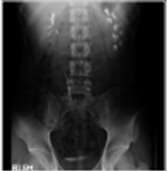

1) 조영제 직전영상: 정찰영상 (scout KUB)으로 석회화병변이 보여 결석이 의심되는 경우, 이후 영상들에서 조영제가 석회화병변을 지나가거나 병변쪽에서 조영제배출의 지연이 있을 경우 결석을 확진할 수 있다. 일반적으로는 그림에서처럼 조영제 직전영상에서는 이상 병변이 없는 경우가 많다.

2) 1~3분 영상: 신조영영상 (Nephrogram)으로 그림과 같이 신장실질이 어느정도 조영이 되어 윤곽이 나타나며, 신우 및 신배가 보이기 시작한다. 그림에서는 좌신의 신배확장증 (calyceal ectasia)이 관찰되며 신배-신우간의 연결이 보이지 않는다.

3) 5~7분 영상: 신배의 둔감 (blunting)이나 게실 (diverticulum)등의 자세한 해부학적 구조를 알 수 있고, 좌우의 대칭여부를 확실히 알 수 있다. 그림에서는 좌신에서 조영제의 배출이 지연됨을 알 수 있다.

5) 지연영상: 15분 영상에서 확인되지 못한 요관의 신우 및 요관의 구조를 파악하는데 도움이 된다. 그림에서는 30분 영상에서 드디어 좌측 요관으로 조영제가 배출됨을 확인할 수 있다. 그림에서는 요관폐색이나 명확한 신우요관의 접합부의 협착소견이 없이 신배확장증소견만 관찰되고 있다.